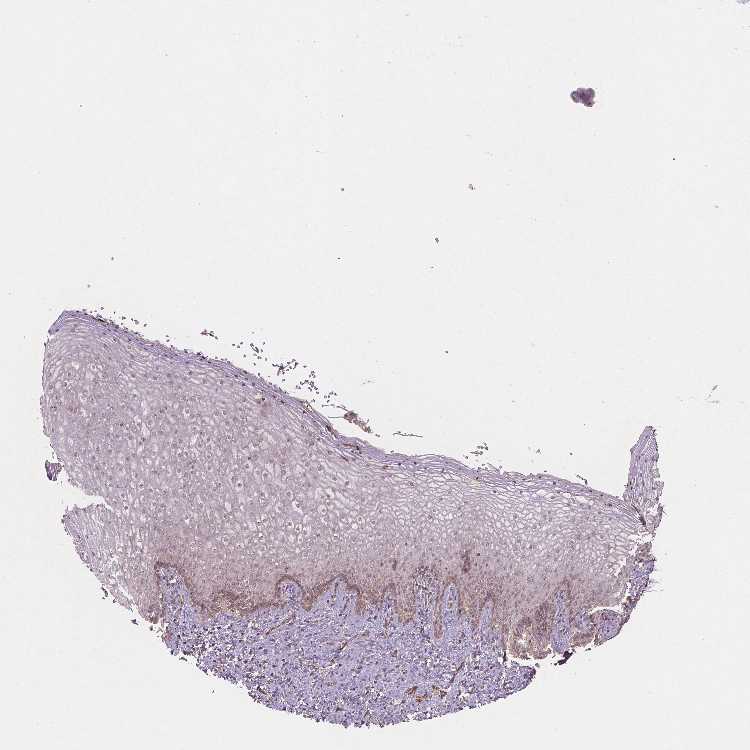

TISSUE PRIMARY DATA VAGINA Show tissue menu

VAGINA - Antibody stainingi

Antibody staining in the annotated cell types in the current human tissue is reported as not detected, low, medium, or high, based on conventional immunohistochemistry profiling in selected tissues. This score is based on the combination of the staining intensity and fraction of stained cells.

Each image is clickable and will lead to virtual microscopy that enables deeper exploration of all samples and also displays staining intensity scores, fraction scores and subcellular localization as well as patient and tissue information for each sample.

Antibody HPA067203Antibody CAB025507Antibody CAB073546

Squamous epithelial cells Not detectedLowLow